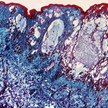

Windpocken/Gürtelrose Varizellen: Ein Virus, zwei Krankheiten

Eine Windpockenimpfung soll auch vor Gürtelrose schützen. Wo aber persistiert das Virus in unserem Körper über viele Jahre, ohne Schaden zu nehmen? Welcher... Mehr»